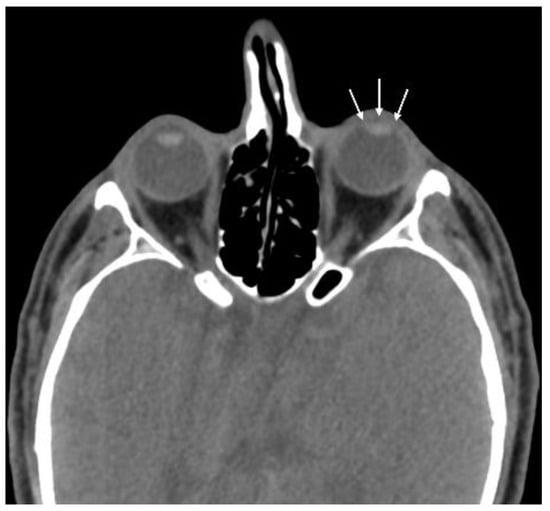

| Globe wall irregularity | 16 (53.3) |

| Asymmetric anterior chamber depth | 16 (53.3) |

| Intraocular air | 3 (10.0) |